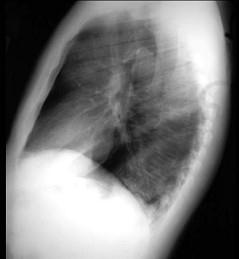

问题 47岁,男,腹泻、体重下降,伴有重症肌无力,请结合胸片和CT选择最可能的诊断 ( )

选项 A、纵隔血肿 B、错构瘤 C、胸腺瘤 D、淋巴瘤 E、胸腺增生

答案 C